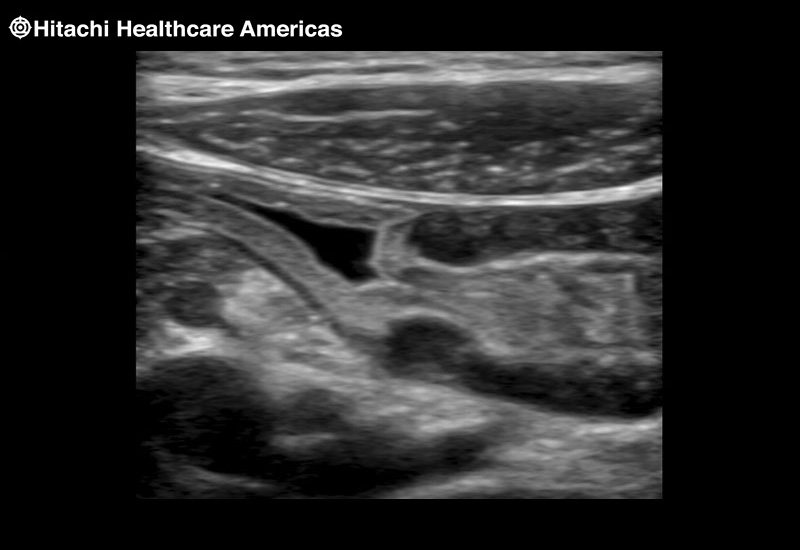

The next level in Robotic Ultrasound

Full wrist articulation with optimized functional length.

A critical function of robotic ultrasound guidance is tumor margin identification. Fujifilm's family of robotic probes all have the optimum location of the attaching mechanism that allows for full wrist articulation of the probe. The result is an increased confidence that the tumor margins have been completely identified.